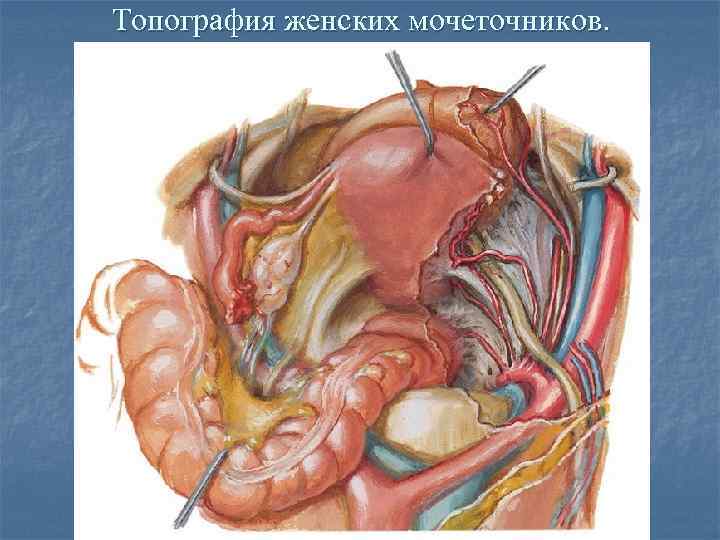

Анатомия малого таза: детальные схемы и изображения

Раздел: Образы вокруг